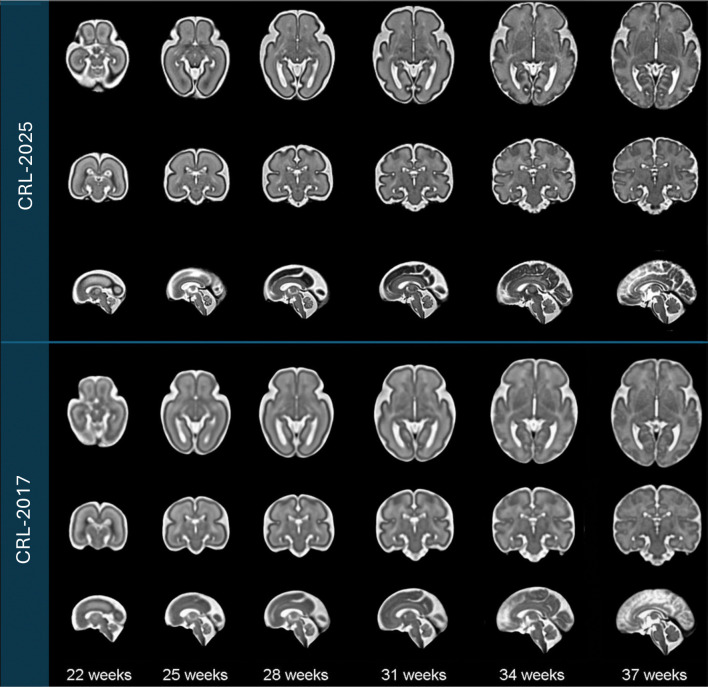

准确描述子宫内大脑发育对于理解典型和非典型神经发育至关重要。在先前构建胎儿脑时空MRI图谱的基础上,我们提出了CRL-2025胎儿脑图谱,这是21至37孕周胎儿脑发育的时空(4D)图谱。该图谱是通过对160个胎儿进行仔细处理的MRI扫描而构建的,这些胎儿具有典型发育的大脑,使用微分形态可变形注册框架与年龄核回归相结合。CRL-2025独特地包括详细的组织分割,瞬态白质区室,并包裹成126个解剖区域。与CRL-2017图谱相比,该图谱提供了显著增强的解剖细节,并与CRL弥散性MRI图谱一起发布,该图谱具有新创建的组织分割和标签,以及用于细粒度胎儿脑MRI分割的基于深度学习的多类分割模型。CRL-2025图谱及其相关工具为胎儿脑MRI分割、分组分析和早期神经发育研究提供了一个强大且可扩展的平台,这些材料公开发布以支持更广泛的研究社区。

Accurate characterization of in-utero brain development is essential for understanding typical and atypical neurodevelopment. Building upon previous efforts to construct spatiotemporal fetal brain MRI atlases, we present the CRL-2025 fetal brain atlas, which is a spatiotemporal (4D) atlas of the developing fetal brain between 21 and 37 gestational weeks. This atlas is constructed from carefully processed MRI scans of 160 fetuses with typically-developing brains using a diffeomorphic deformable registration framework integrated with kernel regression on age. CRL-2025 uniquely includes detailed tissue segmentations, transient white matter compartments, and parcellation into 126 anatomical regions. This atlas offers significantly enhanced anatomical details over the CRL-2017 atlas, and is released along with the CRL diffusion MRI atlas with its newly created tissue segmentation and labels as well as deep learning-based multiclass segmentation models for fine-grained fetal brain MRI segmentation. The CRL-2025 atlas and its associated tools provide a robust and scalable platform for fetal brain MRI segmentation, groupwise analysis, and early neurodevelopmental research, and these materials are publicly released to support the broader research community.